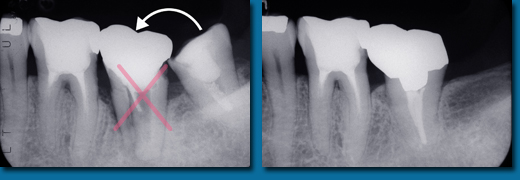

歯並びが悪くなってから治療することを歯列矯正といいますが、乳歯の頃から出てくる歯並びが悪くなる兆候を早期に発見しそれを改善しながらきれいな歯並びの永久歯にしていくことを咬合育成といいます。専門的には歯列矯正と咬合育成は別の物と区別されています。咬合育成は歯並びの予防と考えられ当医院では積極的に取り組み、多くの歯並びの良い子供が育っています。写真の左は乳歯の時、右が永久歯になった時のものです。

咬合育成でおこなうひとつの治療に顎を拡げて永久歯の入るスペースを作るというものがあります。

歯並びの悪い人の多くは顎が小さくて永久歯が並びきらないことが原因になっています。

成長が終わってから矯正治療を受けた方のほとんどが永久歯を4本抜歯してスペースを作って歯並びをきれいにしますが高齢になって歯を失いはじめると最初から歯が4本少ないことは咀嚼をする上でかなりのハンディキャップになります。

なるべく歯を抜かないできれいな歯並びにするには成長期に骨を刺激し、顎を拡げることです。

乳歯から永久歯への生え替わりは6歳くらいから上下の前歯4本から始まり、そして10歳ころから犬歯、奥歯と生え替わり12歳ころで終わります。

はじめに前歯の4本がきれいに並ばなければその後の犬歯、奥歯の生え替わりで歯並びはどんどん悪くなってしまいます。

そのため上下の前歯4本が生え替わる時期に顎を拡げ、きれいに並べておく必要があります。

あまり知られていませんが永久歯の奥歯は乳歯よりも小さいので前歯4本がきれいに並んでいれば奥歯はほとんどがきれいに並びます。

乳歯の時からスペース不足の傾向はでているので個人差はありますが5歳くらいからなるべく早く開始すると安心です。

遅くても8歳になる前には始めなければこの治療法は選択できません。